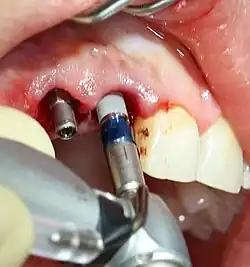

Operationstechnik

Eine zahnärztliche Implantation wird in Lokalanästhesie in der Regel ambulant durchgeführt. An der geplanten Stelle wird nach einem Mukoperiostschnitt die Schleimhaut aufgeklappt und die Implantatbohrung stufenweise nach individuell festgelegter Länge und Durchmesser aufbereitet. Zur Vermeidung einer Überhitzung des Knochens wird die Präparation mit geringer Drehzahl des rotierenden Instrumentes, geringem Druck und permanenter Kühlung mit physiologischer Kochsalzlösung ausgeführt.

Das Implantat wird mit Hilfe eines Drehmomentschlüssels eingebracht. Je nach Knochenqualität sollen dabei bis zu 55 N·cm angewendet werden, um die nötige Primärstabilität zu erreichen. Nach dem Einbringen wird das Zahnfleisch wieder vernäht. Bei entsprechender Nachsorge (kühle Umschläge, Medikamente) lassen sich Komplikationen (Schwellungen usw.) weitgehend vermeiden. Nach zehn Tagen ist die äußere Wundheilung normalerweise abgeschlossen. Eine unbelastete Einheilphase, abhängig von der Knochenqualität, schließt sich an.[23] In der Einheilphase wird ein provisorischer Zahnersatz eingegliedert.

Beispiel für eine zementierte Implantatbrücke auf zwei Implantaten im Unterkiefer

Eingeschraubte Abutments auf Implantaten kurz vor Einsetzen einer Implantatbrücke